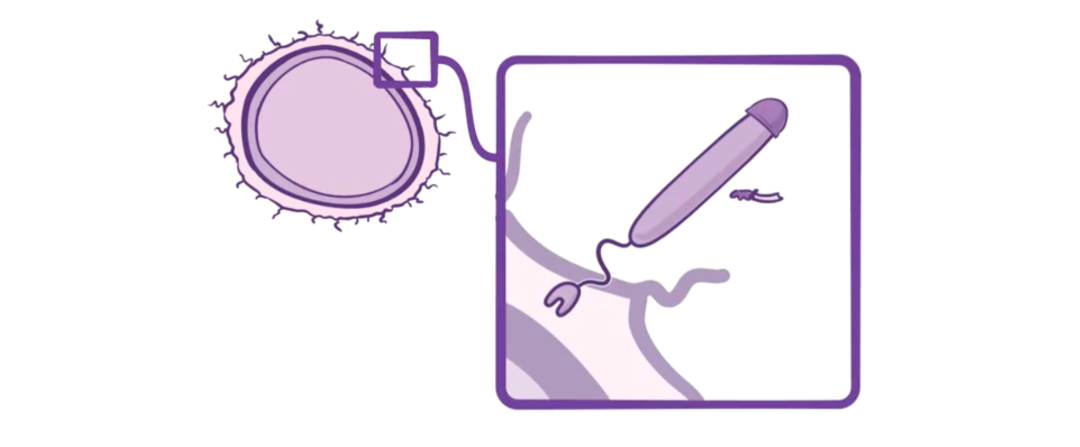

首先,肺炎链球菌有荚膜,也就是说它表面被一层多糖结构覆盖。

荚膜上有菌毛和纤毛,这些毛发样突起可以帮助细菌附着在宿主细胞上。

一旦附着在如鼻咽部或中耳等黏膜表面,肺炎链球菌就能繁殖并形成生物膜。